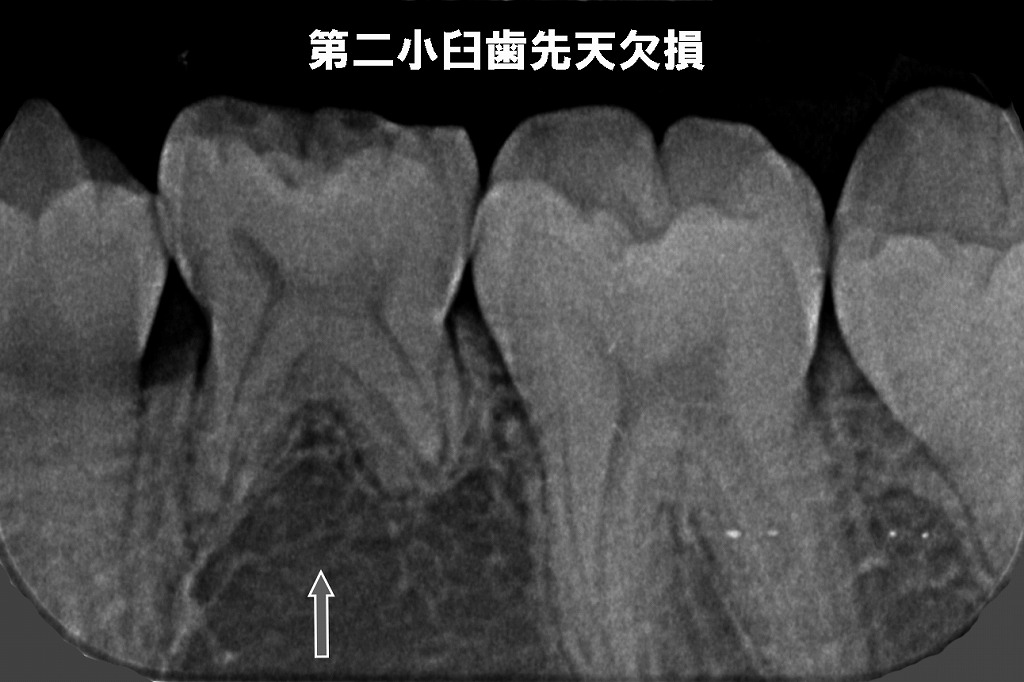

🦷 先天欠損

このデンタルX線写真は、下顎の小臼歯部を撮影したものです。

中央あたりに本来あるはずの第二小臼歯(5番)が写っておらず、歯胚も確認できません。

矢印で示されている部分には、通常であれば第二小臼歯の歯胚(これから生える歯の種)が存在します。

✔ 見られる特徴

- 両隣の歯(第一小臼歯・第一大臼歯)は正常に確認できる

- しかし、その間にあるべき第二小臼歯の歯胚が欠如

✔ 先天欠損とは

生まれつき永久歯の一部が作られない状態。

日本では特に**下顎第二小臼歯(下の5番)**は先天欠損が起こりやすい部位のひとつです。

✔ 臨床的に予想されること

- 将来的に乳歯が長期間残る可能性

- 歯列不正(スペース不足・かみ合わせのズレ)が起きやすい

- 咬合や矯正治療の計画に深く関与する重要所見